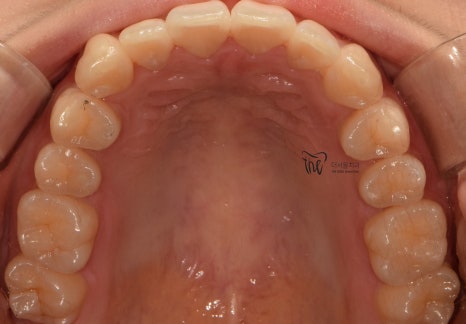

치열이 고르게 바뀐거 뿐만이 아니라

앞니들이 많이 앞쪽으로 뻐드러졌던

모습의 변화를 함께 볼 수 있으며

처음에 오셨을 때와는 다르게,

구강 내 어금니들이 위, 아래로 서로 다

고르게 다 맞물릴 수 있도록 바뀐 모습 또한

한번에 보실 수 있습니다.